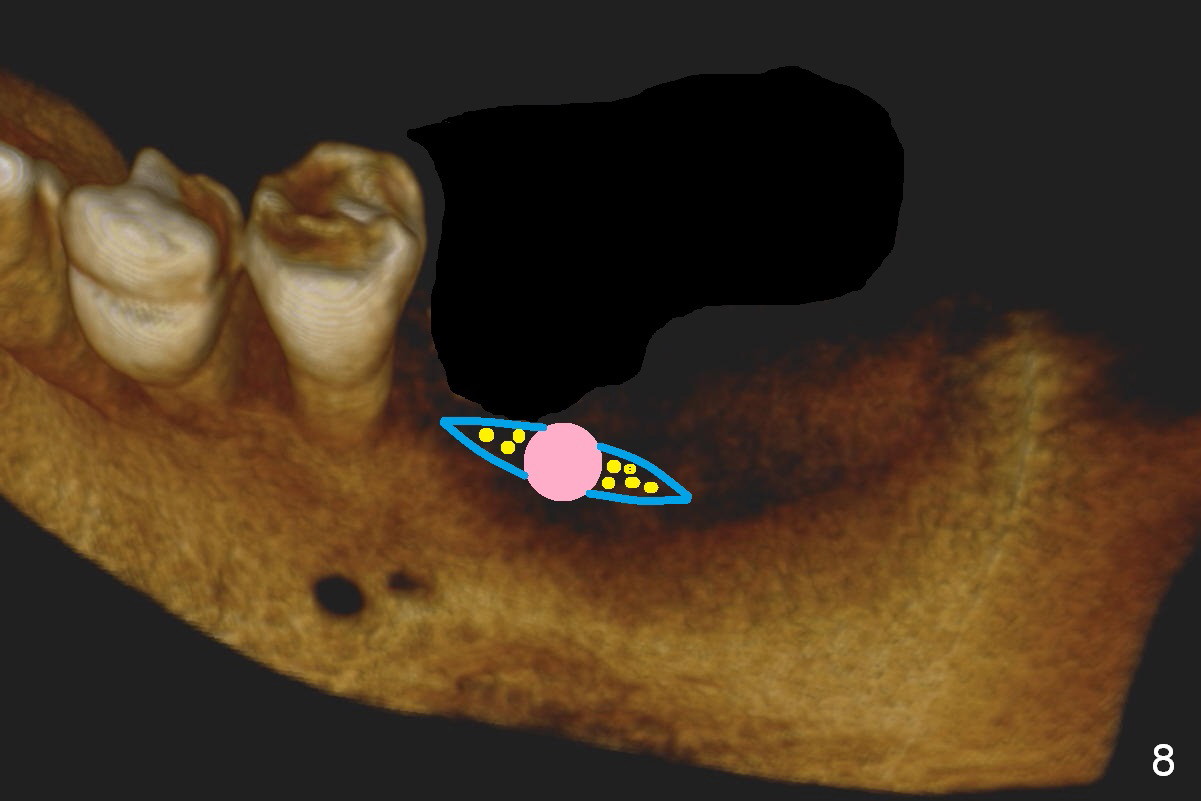

CBCT 3-D image taken with scan stents at the sites of #18 and 19 shows 2 Mental Foramina (Fig.1 *) in the left mandible.  Both sagittal (Fig.2) and coronal (Fig.3) sections show low density at the crest of #19 of a 55-year-old man (arrowheads).  The crest is also narrow.  After making an initial osteotomy through the stent (Fig.4 red arrow), remove the latter (Fig.5).  Ridge split is initiated with wheel saws (Fig.6 blue line).  The osteotomy is enlarged with bone expanders (Fig.7 green circle) with ridge split (blue lines).  Finally an implant is placed (Fig.8 pink circle) with placement of bone graft in the space of the ridge split (yellow circles).